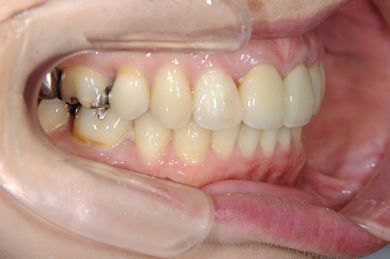

全顎矯正治療+セラミック治療

| 主訴 | 出っ歯 上顎前歯の並び | ||||||||||||||||||||||||||||||||

| 治療方針 | 上下歯牙がだいぶ前にでていて口が閉じづらい状態でした。なるべく金属が入っている歯を抜歯したいので、上下左右第二小臼歯を抜歯して、その隙間を利用して、口元をさげていきました。また、口元を最善の状態にうるために、抜歯スペースを使用したあと、上下左右のインプラントアンカー(釘)でより一層口元を後ろにさげていきました。ただの抜歯ケースよりだいぶ口元が下がっているのが分かります。抜歯したスペースががたつき(叢生量)で使用してしまう場合には、このような方法でより口元をさげることができます。お顔立ちがとてもよくなりました。とても協力していただけたので、しっかりと良くなることができました。 | ||||||||||||||||||||||||||||||||

| 治療内容 | 唇側矯正(ホワイト・上下左右第二小臼歯抜歯・上下インプラントアンカー)、オールセラミッククラウン1本(オールセラミック用土台1本)、ジルコニアフレームオールセラミッククラウン1本 | ||||||||||||||||||||||||||||||||